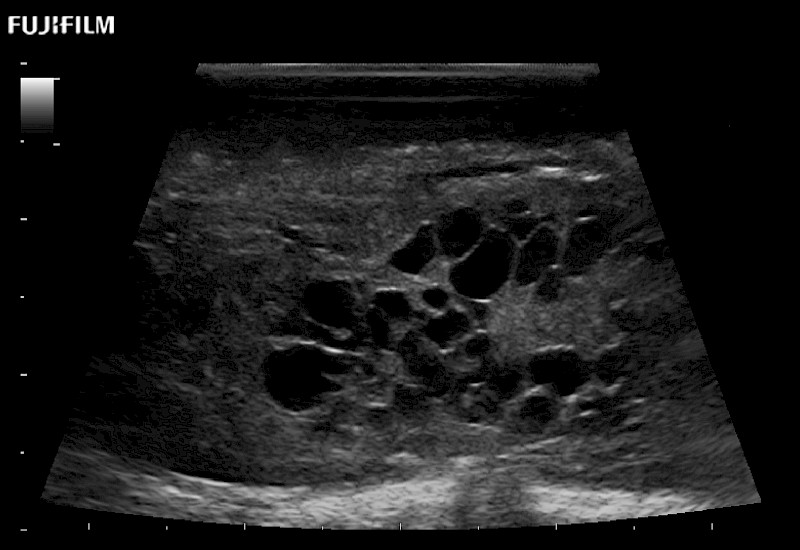

The world's only phased array burr-hole transducer that is ideal for scanning during burr-hole guidance procedures.

Main Specifications: